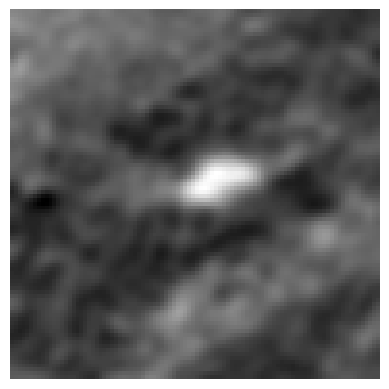

Refer to caption

(a)

(b)

(c)

(d)

Figure 3: Representation of generated features by DINO-LG model trained with label-guided approach and standard DINO training. Figure (a)𝑎(a)( italic_a ) represents a CT slice having calcified area and (b)𝑏(b)( italic_b ) shows annotated area for calcification. Figure (c)𝑐(c)( italic_c ) and (d)𝑑(d)( italic_d ) represent visualization of overlay self-attention maps are generated by standard DINO model and DINO-LG model, respectively.